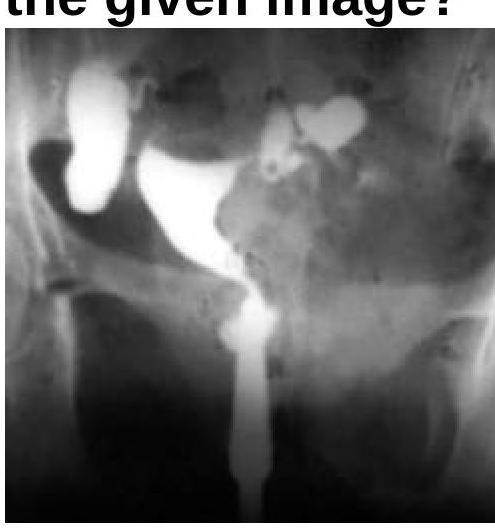

Question 5: What will be the Hysterosalpingogram (HSG) finding?

Explanation: ***Hydrosalpinx*** - The image, likely a hysterosalpingogram (HSG), shows a **dilated and fluid-filled fallopian tube** with no spillage of contrast into the peritoneal cavity, which is characteristic of hydrosalpinx. - The **contrast media fills the tubal lumen** but is unable to egress, indicating distal tubal obstruction and fluid accumulation. *Cornual block* - A cornual block would present as **obstruction at the uterine ostium** of the fallopian tube, preventing contrast from entering the tubal lumen. - In this image, contrast has clearly entered and dilated the fallopian tube, ruling out a cornual block. *Normal findings* - Normal HSG findings would show **patent fallopian tubes** with free spill of contrast into the peritoneal cavity. - The visible **dilation** and **lack of spill** in the image are distinctly abnormal. *Bicornuate uterus* - A bicornuate uterus is a **congenital uterine anomaly** characterized by two separate uterine horns. - While the uterus appears somewhat irregular, the dominant feature is the dilated fallopian tube, which is not a hallmark of a bicornuate uterus.